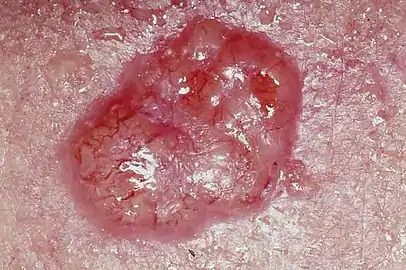

Basal-cell carcinoma (BCC), also known as basal-cell cancer, basalioma[7] or rodent ulcer,[8] is the most common type of skin cancer.[2] It often appears as a painless raised area of skin, which may be shiny with small blood vessels running over it.[1] It may also present as a raised area with ulceration.[1] Basal-cell cancer grows slowly and can damage the tissue around it, but it is unlikely to spread to distant areas or result in death.[9]

Individuals with a basal-cell carcinoma typically present with a shiny, pearly skin nodule. However, superficial basal-cell cancer can present as a red patch similar to eczema. Infiltrative or morpheaform basal-cell cancers can present as a skin thickening or scar tissue – making diagnosis difficult without using tactile sensation and a skin biopsy. It is often difficult to visually distinguish basal-cell cancer from acne scar, actinic elastosis, and recent cryodestruction inflammation.[14]